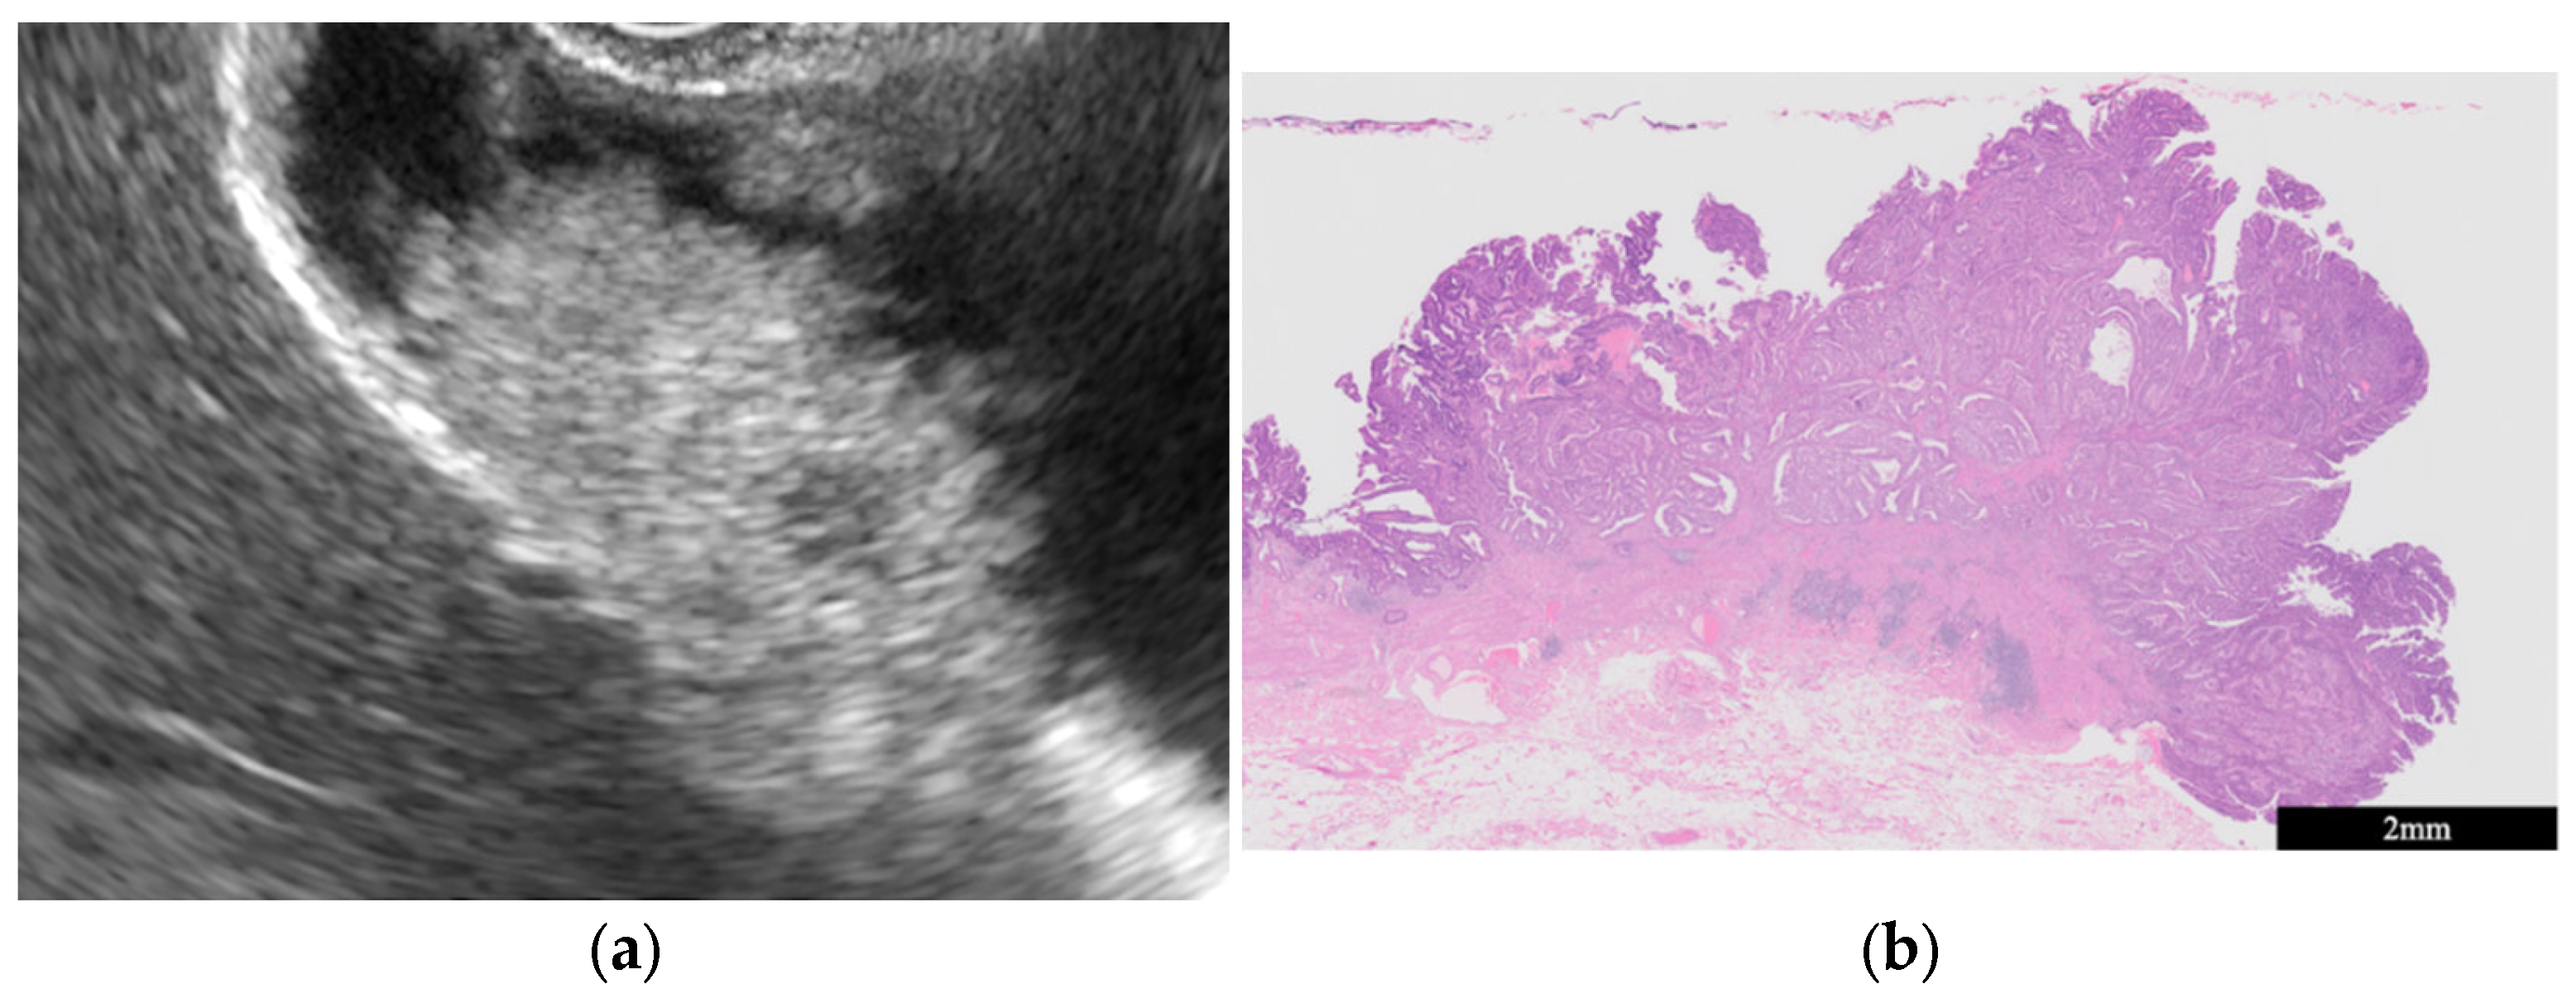

- GB mucosal hyperplasia associated with pancreaticobiliary maljunction (PBM) (Figure 4)

| GB mucosal hyperplasia associated with pancreaticobiliary maljunction | Smooth | Uniform hypoechogenicity | Preserved |